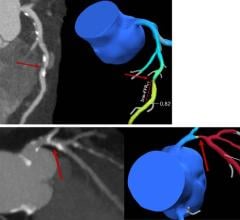

U.S. Electronics Inc. will introduce two new medical-grade high-luminance monochrome LCD displays, offering a full array of features. The new high-contrast USEI/Totoku ME355i2 3 MP and ME253i2 2 MP monitors support a broad range of diagnostic imaging modalities, including CT, MRI and high-speed 3-D image rendering. Utilizing Totoku’s Luminescence Uniformity Equalizer technology, both models provide consistent light intensity across the entire display face, eliminating uneven brightness at the periphery. An 11.9-bit lookup table (LUT) delivers ultra-high grayscale DICOM conformance for a distortion-free image.